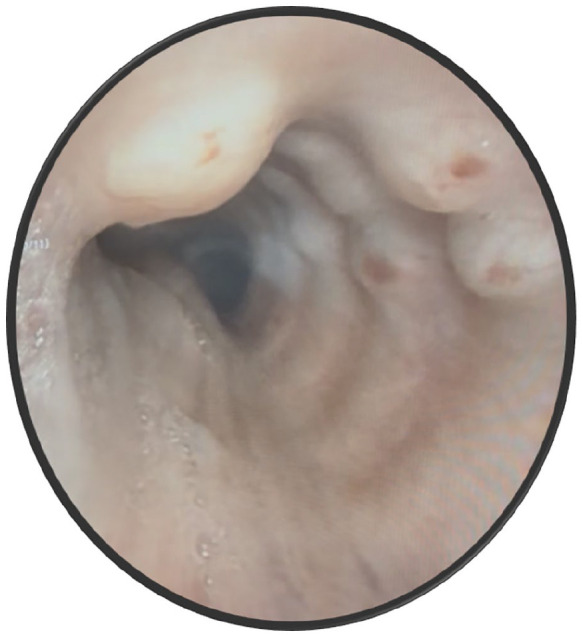

气管支气管骨性软骨病变(TPO)是一种罕见的良性疾病,其特征是存在粘膜下软骨和骨性结节,突出到气管支气管管腔的前壁和侧壁,保留后膜壁。这些结节是偶然发现的影像学和支气管镜检查不相关的呼吸道症状。确切的发病机制尚不清楚,提出了各种假说。最广为接受的说法是慢性炎症导致气管支气管粘膜下层软骨和骨性化生。TPO是罕见的,由于诊断的偶然性,患病率进一步被低估。临床上,患者可能无症状,也可能有非特异性症状,如慢性咳嗽、呼吸困难和反复呼吸道感染。在气管支气管管腔偶然发现结节时,对诊断产生怀疑。诊断是通过支气管镜观察保留后壁的特征性结节病变建立的,可以通过组织病理学检查显示粘膜下软骨形成和骨化来证实。管理一般是保守的,重点是症状缓解和治疗感染。严重的气道阻塞病例可能需要进行先进的支气管镜检查或手术干预。尽管它是良性的,但TPO可以模仿其他严重的气管疾病。了解这种情况对于准确诊断和适当管理至关重要。我们报告一个65岁无症状慢性吸烟者的病例,他在胸部影像学上发现气管结节。支气管镜检查与TPO一致,组织病理学证实了诊断。

Tracheobronchopathia osteochondroplastica (TPO) is a rare, benign condition characterized by the presence of submucosal cartilaginous and osseous nodules protruding into the anterior and lateral walls of the tracheobronchial lumen, sparing the posterior membranous wall. These nodules are incidentally discovered on imaging and bronchoscopy performed for unrelated respiratory symptoms. The exact etiopathogenesis is unclear, with various hypotheses proposed. The most widely accepted one is that chronic inflammation leads to cartilaginous and osseous metaplasia of the tracheobronchial submucosa. TPO is rare, with the prevalence further underestimated due to the incidental nature of the diagnosis. Clinically, patients may be asymptomatic or can have nonspecific symptoms such as chronic cough, dyspnea, and recurrent respiratory infections. Suspicion of the diagnosis arises upon incidental identification of nodules in the tracheobronchial lumen. Diagnosis is established through bronchoscopic visualization of characteristic nodular lesions sparing the posterior wall and can be confirmed by histopathologic examination showing submucosal cartilage formation and ossification. Management is generally conservative, focusing on symptomatic relief and treatment of infections. Severe cases with significant airway obstruction may warrant advanced bronchoscopic procedures or surgical interventions. Despite its benign nature, TPO can mimic other serious tracheal diseases. Awareness of this condition is essential for accurate diagnosis and appropriate management. We present a case of a 65-year-old asymptomatic chronic smoker who was found to have tracheal nodules on thoracic imaging. Bronchoscopic evaluation was consistent with TPO, with histopathology reaffirming the diagnosis.